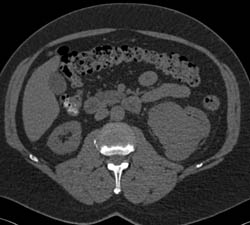

Multiple Renal Arteries to Each Kidney for Renal Donor